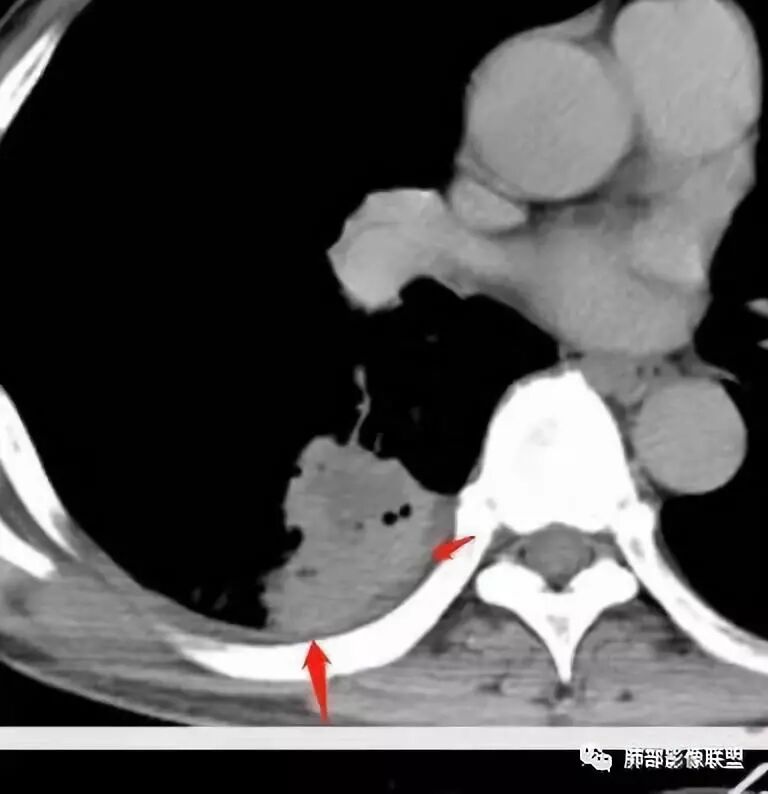

少量积液反衬外壁更好看,靠近胸膜侧有很多积液不连续,断掉,局部膨隆在外面。很大一部分是连续的,但有些部分是不连续的。有膨隆我就很难判断,病灶的膨隆是张力引起的,还是远端栽赃引起的?局部的胸膜有变化的。所以我怀疑有栽赃的趋势,为什么说趋势,是因为没看到外面一个侵犯的迹象,但是层厚原因我有些地方我不敢说,有没有侵犯。

南边:

你看我标的这个地方,我就觉得这个病灶有侵犯性,附近旁边都有一个低密度线影,局部就没了,病灶似乎直接到个肋骨的胸膜脂肪间隙下,这些地方都有类似迹象,把它当成一个大的肿块,有分叶,近端有坏死、空洞,壁外围还有有些毛糙,腔内也有些索条影。颅脑内像个转移瘤的特点,转移瘤,淋巴瘤,脓肿?脓肿腔内脓液粘稠,弥散受限,这个腔内DWI不高,这个让我犹豫.按理脓肿也要考虑.